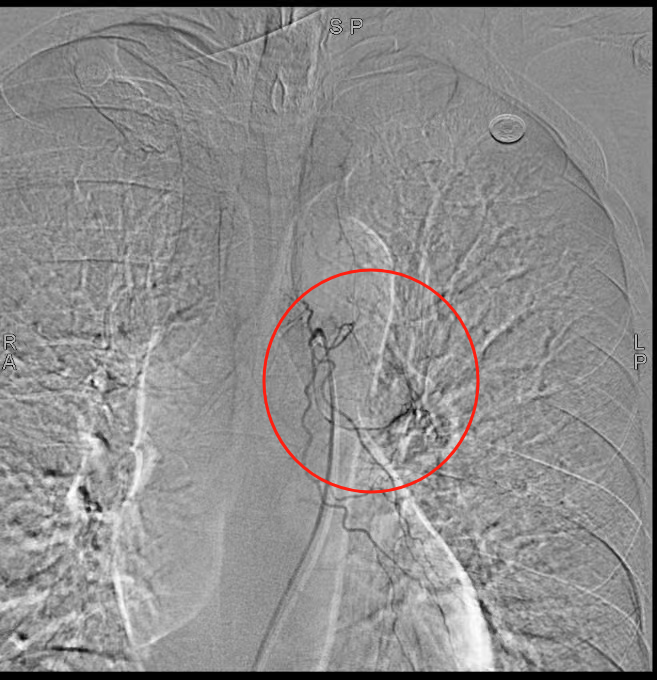

1.血管介入止血:通过支气管动脉栓塞术紧急控制出血风险;

“支气管淀粉样变发病率极低,极易误诊漏诊!”我院呼吸与危重症医学科副主任(主持工作)王开金副主任医师介绍,该病由淀粉样物质异常沉积于气道引发,临床表现缺乏特异性,确诊必须依赖病理活检。“此例患者出血风险极高,活检操作犹如‘刀尖起舞’。”王开金表示,团队通过血管介入止血、支气管镜精准定位和快速病理检测,实现了“诊断-治疗”一体化,为患者抢得生机。